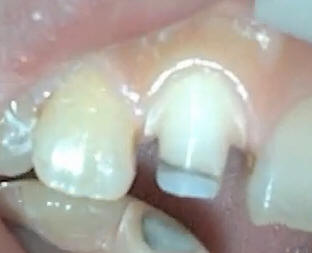

Levando el hombro

a subgingival solo en vestibular |

Con puntas de diamante

de grano extrafino se elimina el esmalte sin soporte en mesial y distal |